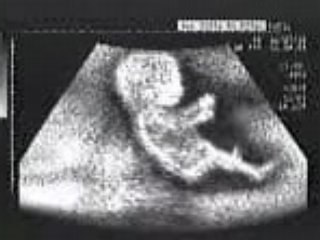

Ecografia Ostetrica 20 settimane